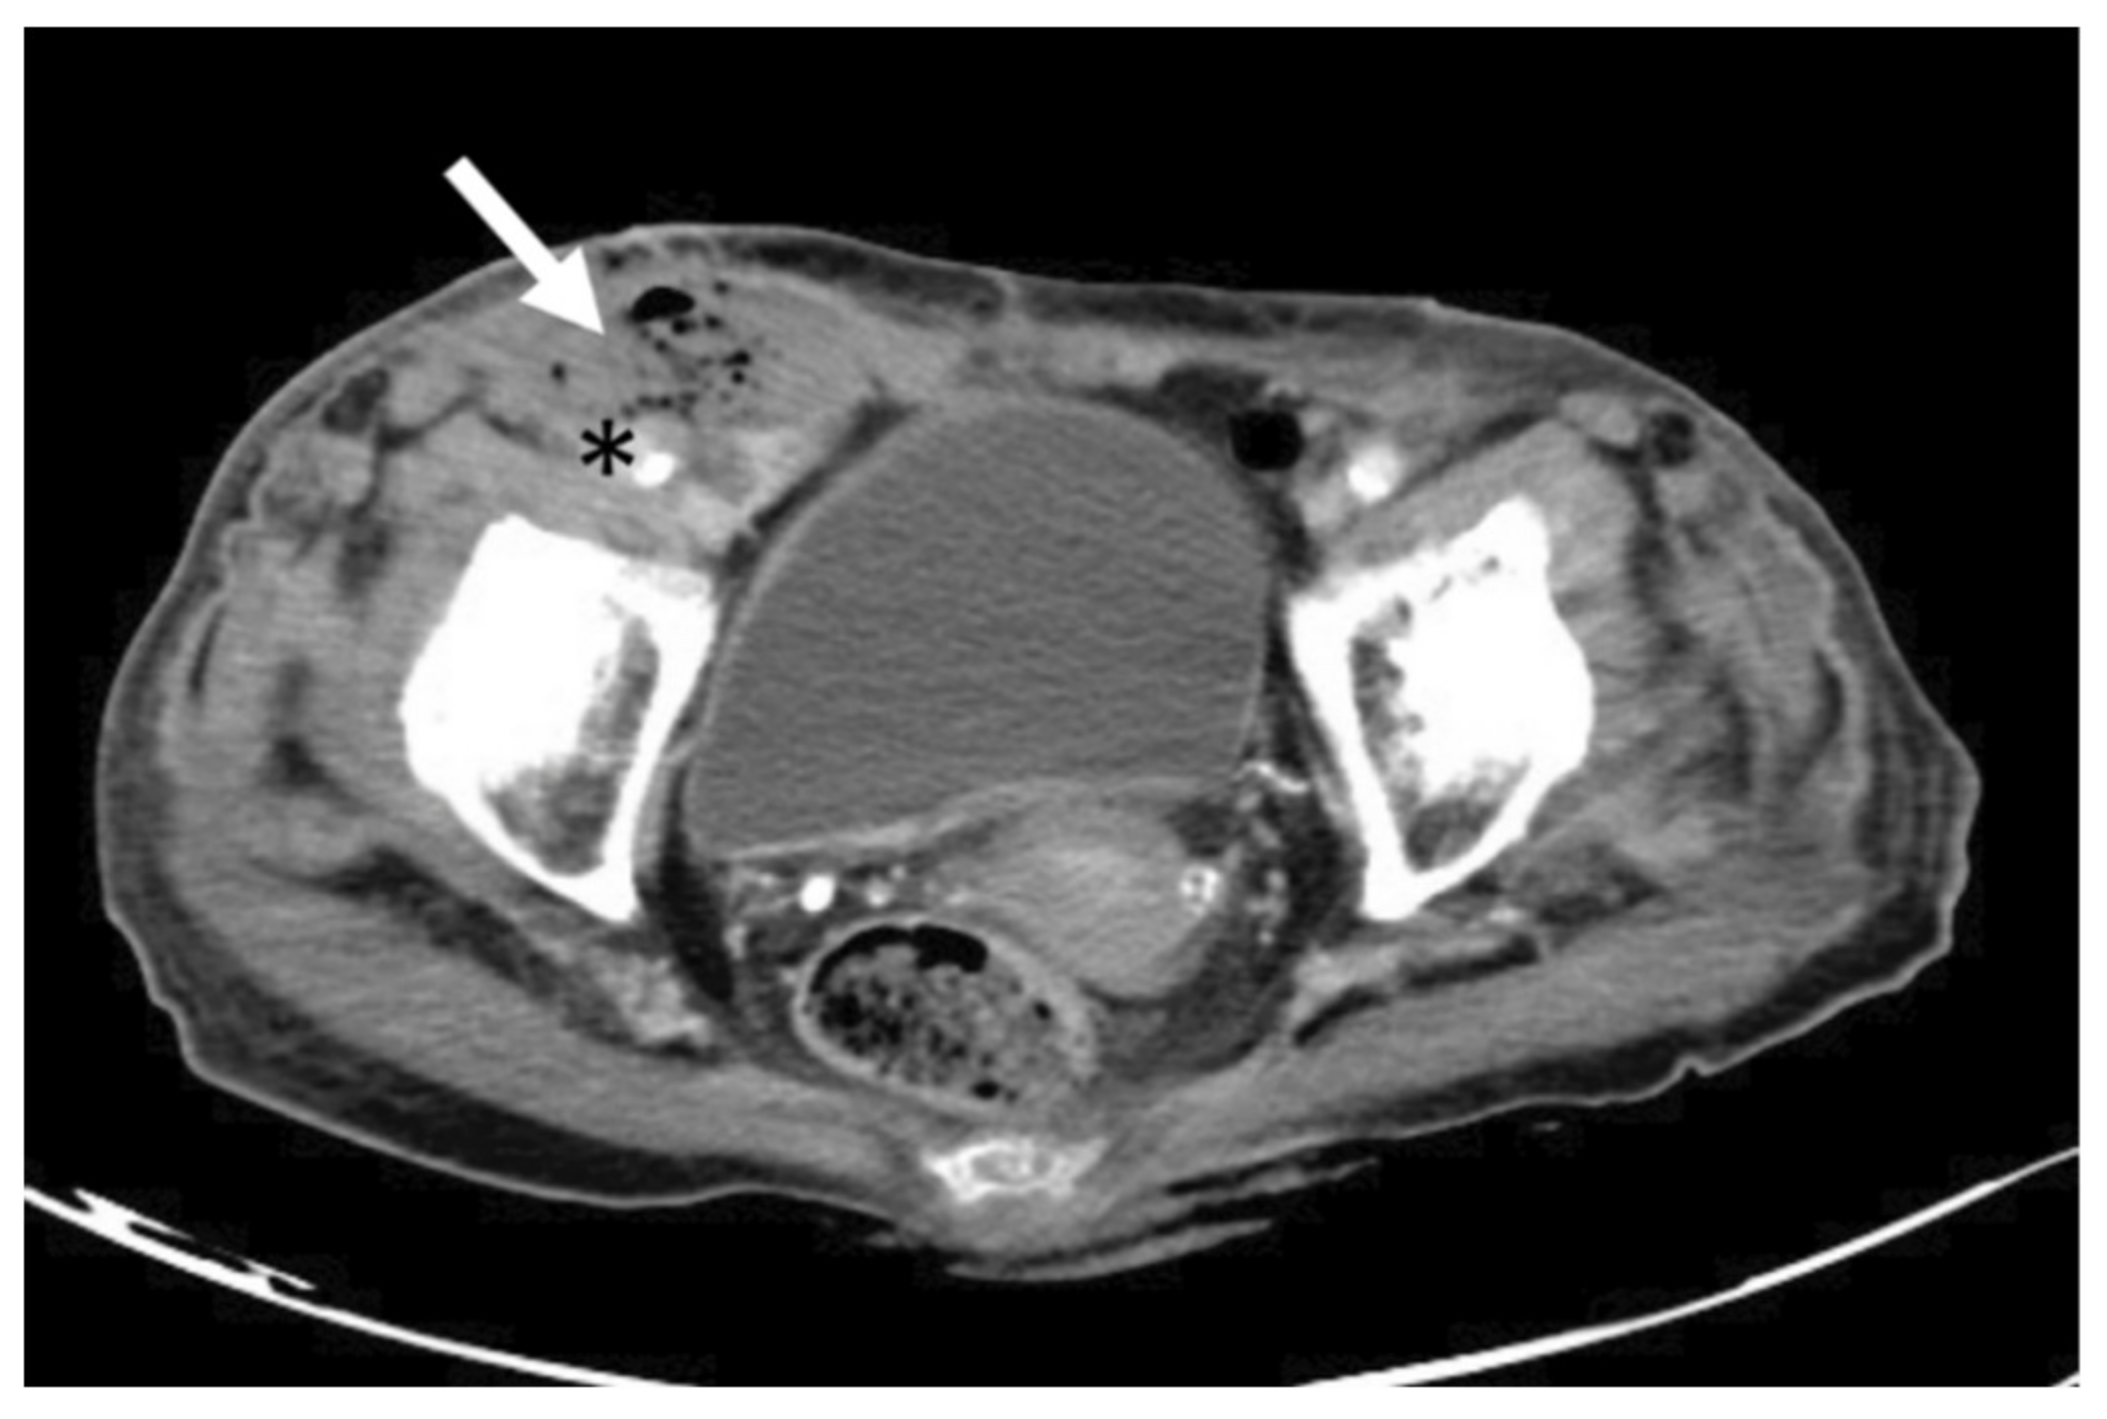

Computed tomography angiography (CTA) showed a hematoma over her right femoral region, with free air surrounding the right femoral artery (Figure 2).

Figure 2. The transverse view of Computed tomography angiography revealed an emphysematous hematoma (arrow) close to right femoral artery (asterisk).